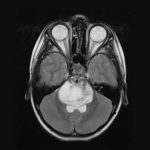

(Leucemia-Immagine Credit Public Domain).